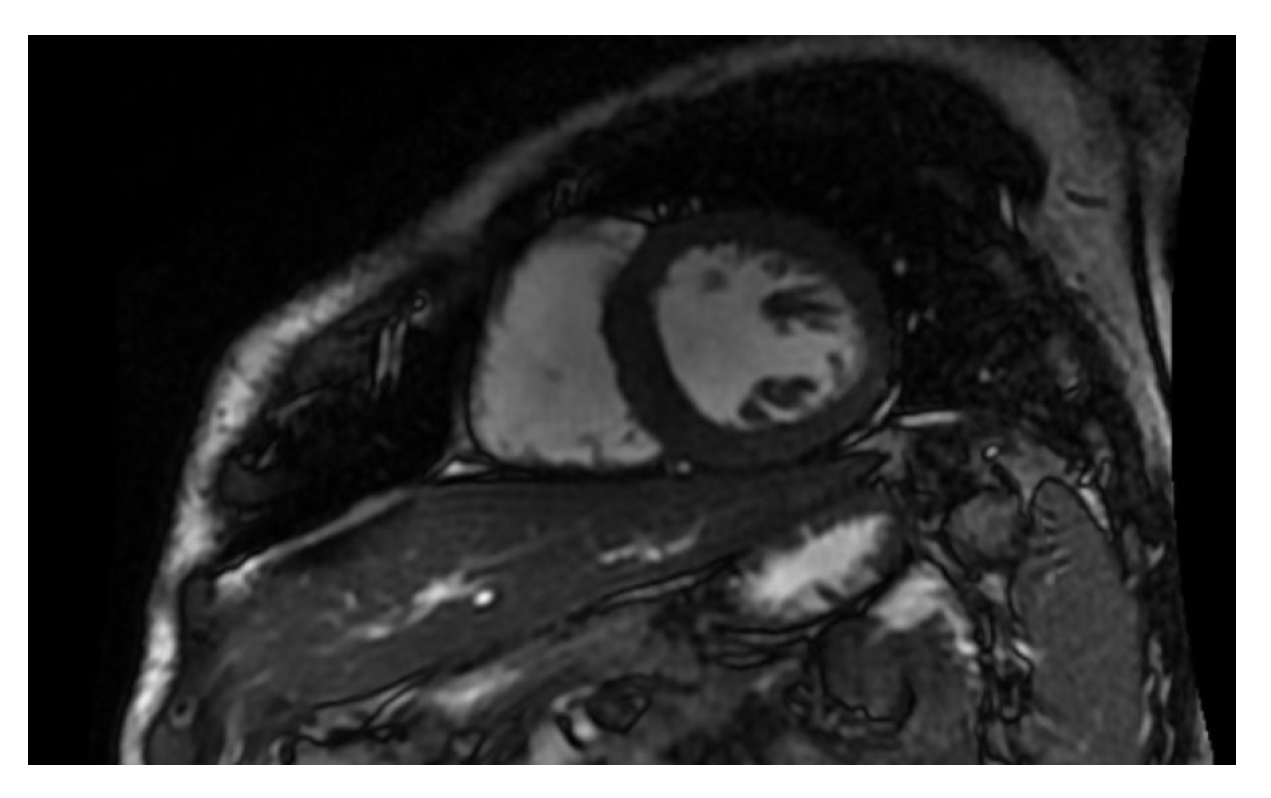

- Cardiac-MRI parameters (tissue evaluation, ventricular functional analysis, valve condition, and atrial dimension);

2.7. MR Setting

| CT Settings | MR Settings |

| • Collimation 64 × 0.6 mm | • 1.5 Tesla Magnet |

| • Pitch 0.2 to 0.5 | • Slice thickness 8 mm |

| • Gantry rotation time 3.30 s | • Slice spacing 2 mm |

| • Pipe current 330 mA | • T1 FS sequences 10 min after the contrast agent injection |

| • Pipe power 120 kV (patient > 85 kg) or 100 kV (patient < 85 Kg) | • Prospective cardiac synchronization |